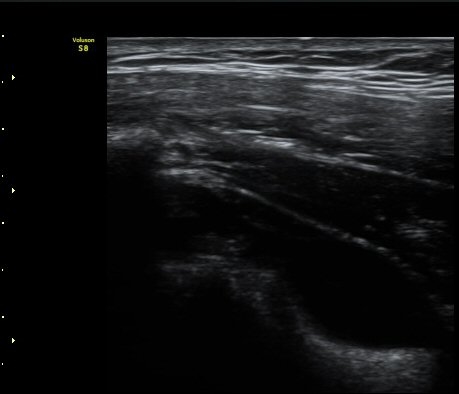

ÃÊÀ½ÆÄ °Ë»ç

2049205267_d18eca99_IMG_20140331_2_1-c.jpg